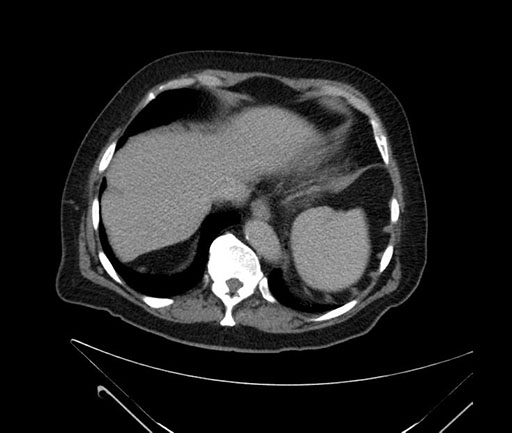

Imaging Analysis

Look through the patient's CT scan to identify any areas of concern for the necessary procedure.

Based on your CT findings, which issue(s) would give reason for "planned slowing down moment(s)" in this case?